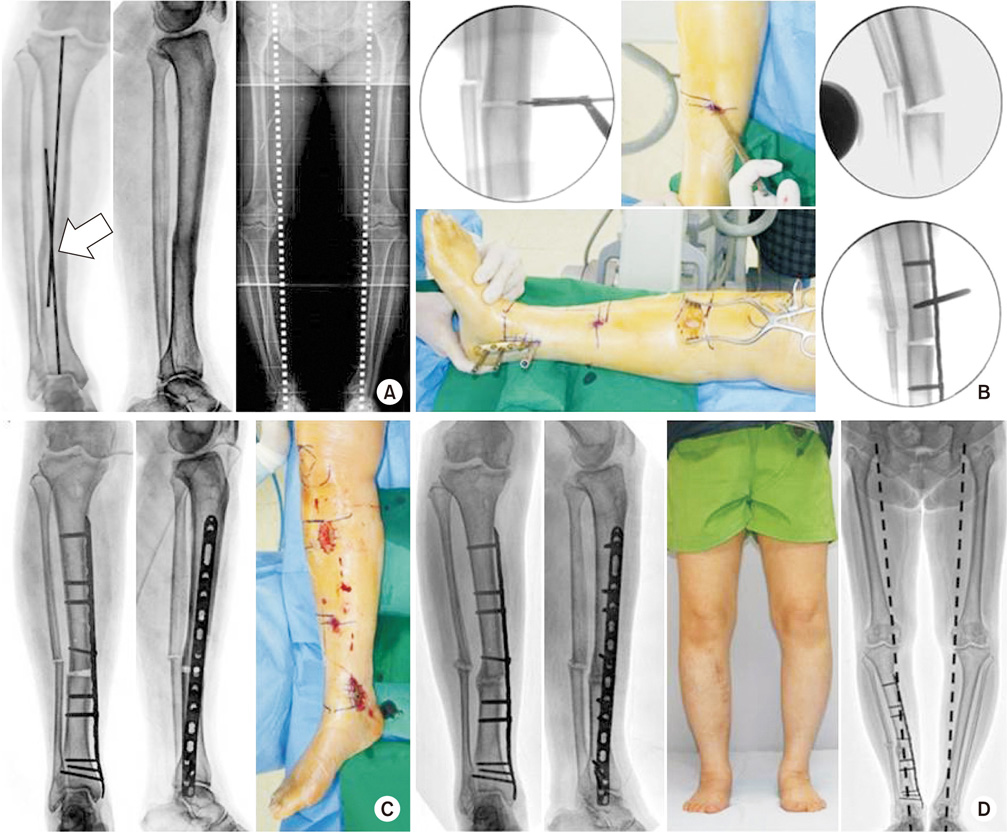

(A) In a 58-year-old female, malunion with varus deformity after tibia shaft fracture was observed. The center of rotation of angulation was confirmed at the tibial shaft (arrow). (B) Percutaneous osteotomy was performed; an open wedge was made to an obtain angular correction, and minimally invasive plate fixation was performed. (C) After open wedge osteotomy, the alignment of the mechanical axis was restored. (D) One year postoperatively, bony union was achieved, and the mechanical axis was recovered similar to that of the contralateral side.

jkfs-30-219-g005.jpg

Fig. 5 (A) In a 58-year-old female, malunion with varus deformity after tibia shaft fracture was observed. The center of rotation of angulation was confirmed at the tibial shaft (arrow). (B) Percutaneous osteotomy was performed; an open wedge was made to an obtain angular correction, and minimally invasive plate fixation was performed. (C) After open wedge osteotomy, the alignment of the mechanical axis was restored. (D) One year postoperatively, bony union was achieved, and the mechanical axis was recovered similar to that of the contralateral side.